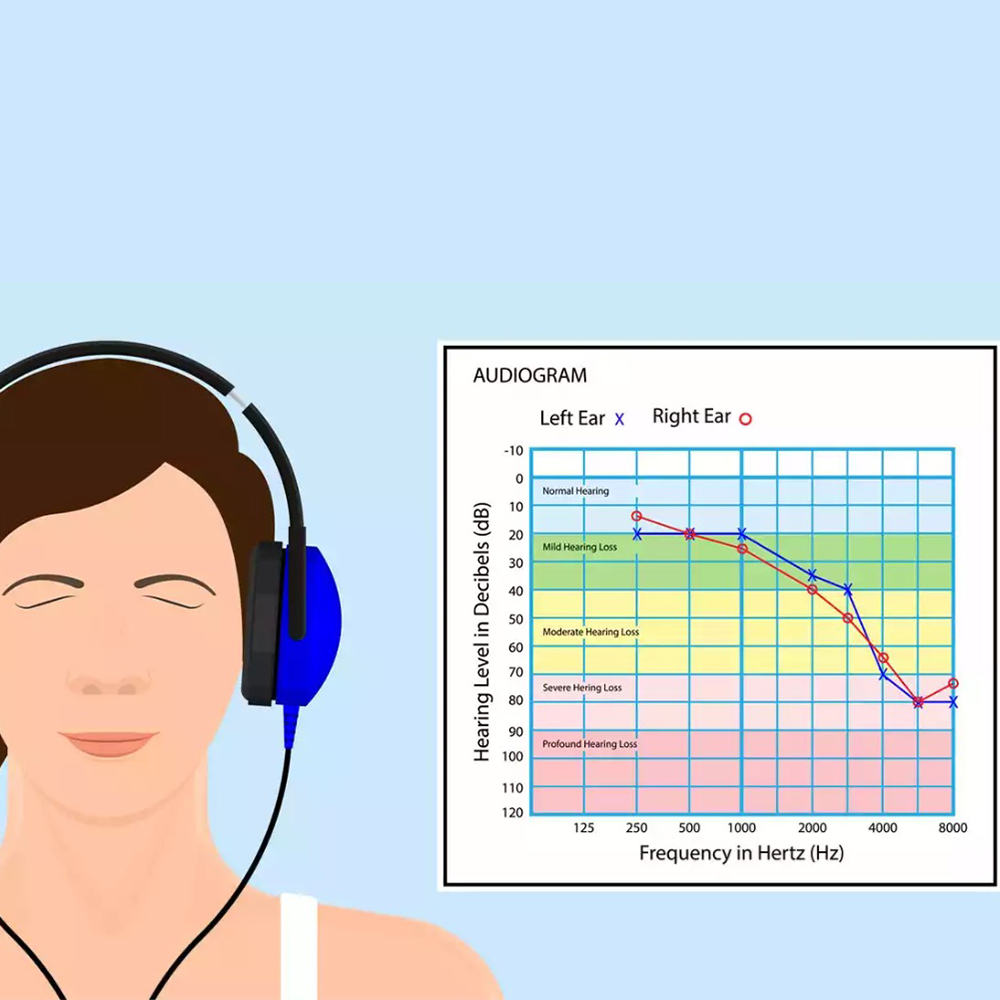

Audio-metric Testing

Audio-metric Testing